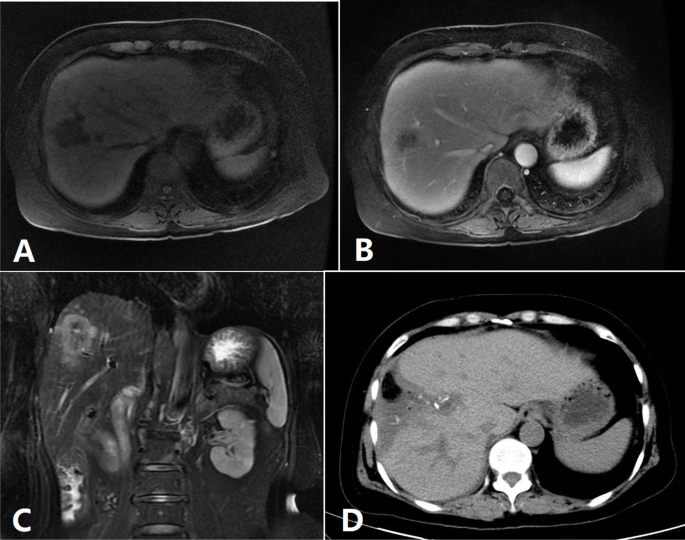

The patient’s position and the layout of the Trocars were according to our previous in our previous research8,9. The surgical technique described in a previous study was used (Fig. 1)13. The hepatic portal plate was exposed after the gallbladder was resected. Thereafter, the liver parenchyma was transected under ultrasonographic guidance to expose and block the Glissonean pedicle of the right anterior lobe. The liver parenchyma was transected along the hepatic ischemic line and the right side of the MHV. The separation of the liver parenchyma was continued along the other side hepatic ischemic line and the left side of the RHV. Preoperative 3D reconstruction was performed to evaluate the relationship between the lesion and hepatic vein, and determine the cutting plane (Fig. 2). Laparoscopic ultrasonography was used to determine the intrahepatic vessel anatomy. The intrahepatic vascular or biliary branches were ligated using clips (Hem-o-lok). We employed the Pringle maneuver when the abovementioned method could not be implemented. Finally, the Glissonean pedicle of the right anterior lobe was divided, and the specimen was removed (Supplementary Fig. 1). The steps of ORAS were similar to those of LRAS. Figure 3 shows the radiological imaging of a patient.